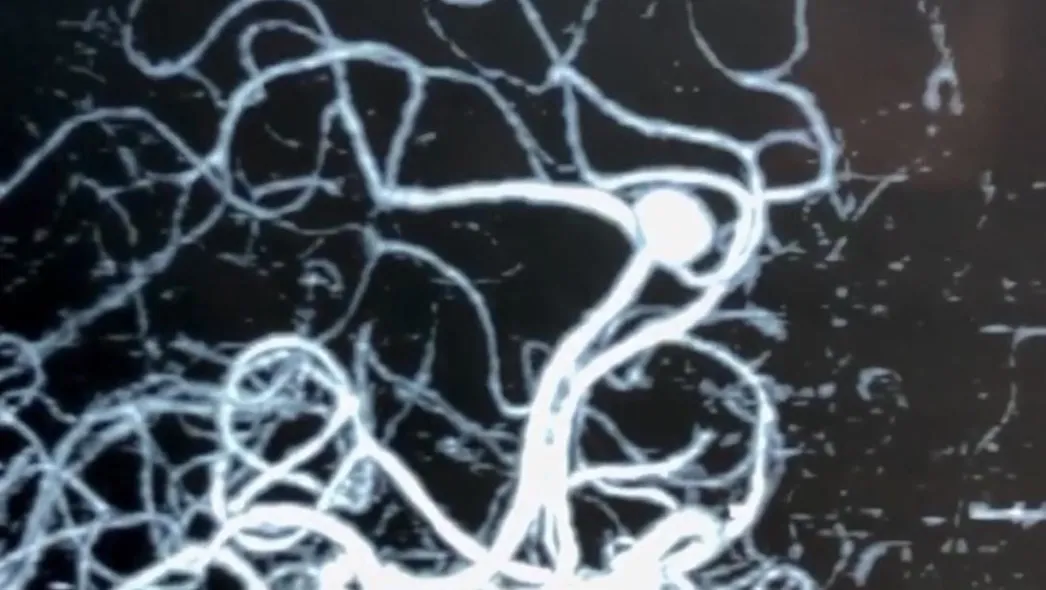

Aneurysms of cerebral arteries are vascular pathologies in which the wall of an artery bulges. According to the shape of the protrusion, saccular and spindle-shaped (fusiform) aneurysms are distinguished. The cause of aneurysms is not known for sure. Among the etiological factors can be congenital predisposition (defects of the muscle layer of the wall of cerebral vessels); atherosclerotic (combined with congenital defects of the wall of cerebral vessels); embolic, infectious, traumatic factors.

Brain MRI, cerebral angiography, CT angiography.